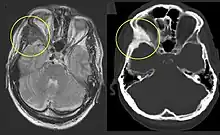

Fibrous dysplasia of the right zygomatic bone (left). Corresponding T2-weighted MRI (left) and CT (right) of the same patient.

Fibrous dysplasia is a mosaic disease that can involve any part or combination of the craniofacial, axillary, and/or appendicular skeleton.[7] The type and severity of the complications therefore depend on the location and extent of the affected skeleton. The clinical spectrum is very broad, ranging from an isolated, asymptomatic monostotic lesion discovered incidentally, to severe disabling disease involving practically the entire skeleton and leading to loss of vision, hearing, and/or mobility.

On x-ray, fibrous dysplasia appears as bubbly lytic lesions, or a ground glass appearance. Computerized tomography (CT) or magnetic resonance imaging (MRI) scans may be used to determine how extensively bones are affected. CT can better demonstrate the typical "ground glass" appearance, which is a highly specific radiological finding, while MRI can show cystic areas with fluid contents.[15] A bone scan uses radioactive tracers, which are injected into your bloodstream. The damaged parts of bones take up more of the tracer, which show up more brightly on the scan. A biopsy, which uses a hollow needle to remove a small piece of the affected bone for laboratory analysis, can diagnose fibrous dysplasia definitely.